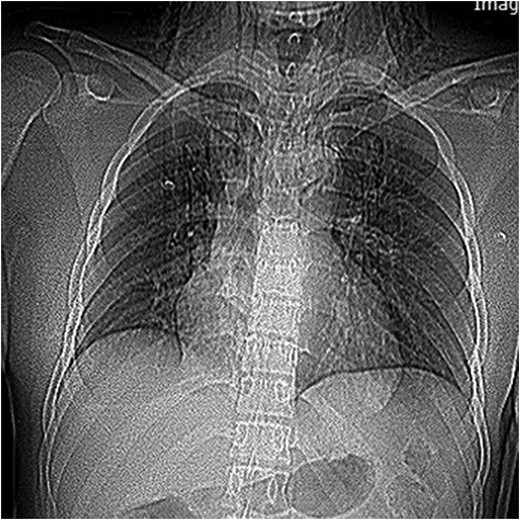

A 25-year-old man arrived in the emergency room 8 h after a motor accident in which a rope was wrapped around his neck. Initial pulse oximetry saturation (SpO2) was 94%. The vital signs included a blood pressure of 122/80 mmHg, a heart rate of 98 beats/min, a respiratory rate of 23 breaths/min, and an axillary temperature of 36.2°C. Because of the good general and respiratory condition of the patient on admission, the pathognomonic signs of laryngeal injury were not noticed. Patient had skin contusion and moderate crepitus on his neck area (Fig. 1). His phonation was normal without dyspnea, cough, hemoptysis or hoarseness. Pneumomediastinum and subcutaneous emphysema were noted on a supine chest radiograph (Fig. 2). Computed tomographic (CT) scan of the neck and chest revealed pneumomediastinum, subcutaneous emphysema in the neck and distortion of laryngotracheal framework (Fig. 3). Flexible bronchoscopy showed cricotracheal transection with normal movement of true vocal cord. At the same setting, endotracheal tube was advanced distal to the transection site under bronchoscopic guide (Video). Neck exploration demonstrated complete cricotracheal separation (Fig. 4). The area was debrided and primary cricotracheal end-to-end anastomosis was performed. The patient was extubated 2 days after the surgery. Fiberoptic bronchoscopy on Days 20 and 90 showed that the tracheal injury healed completely with no apparent proliferation of granulation tissue.

Supin chest radiograph showing pneumomediastinum and neck subcutaneous emphysema.